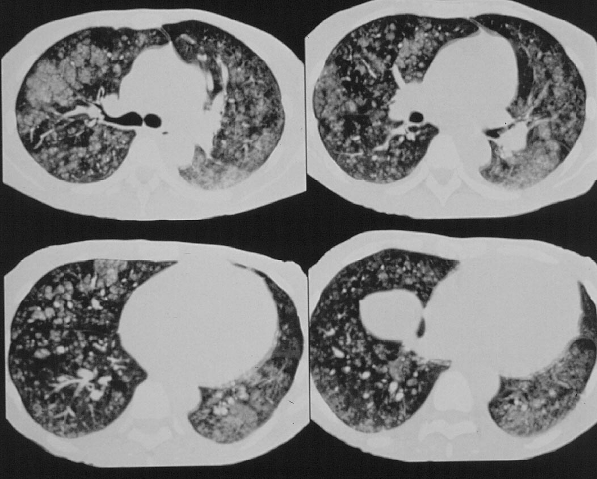

Metastatic Calcification to Lung in Chronic Renal Disease